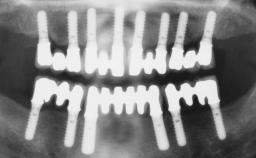

A 68-year-old, completely edentulous male patient presented for evaluation and treatment options. He reported excellent general health and was taking no regular medication. He had been edentulous for approximately 12 years, having lost his teeth to periodontal disease and dental caries. The patient’s chief complaint was incompetent function. His secondary concerns included his appearance and the desire for a predictable outcome. He attributed his reduced functional capacity to his lower complete denture, which he described as poor. He was particularly concerned with the denture’s instability and poor fit. In general terms, he was satisfied with the maxillary complete prosthesis. The maxillary prosthesis was characterized by adequate retention, stability, and support, although the fit was considered less than ideal.

- Surgical SAC classification

- Advanced

- Prosthodontic SAC classification

- Complex